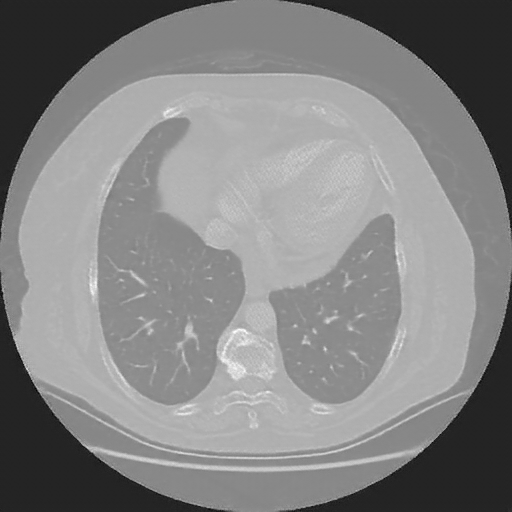

Original VENOUS CT scan

Mediastinum window (WL 40, WW 400 β†’ Low βˆ’160, High +240)